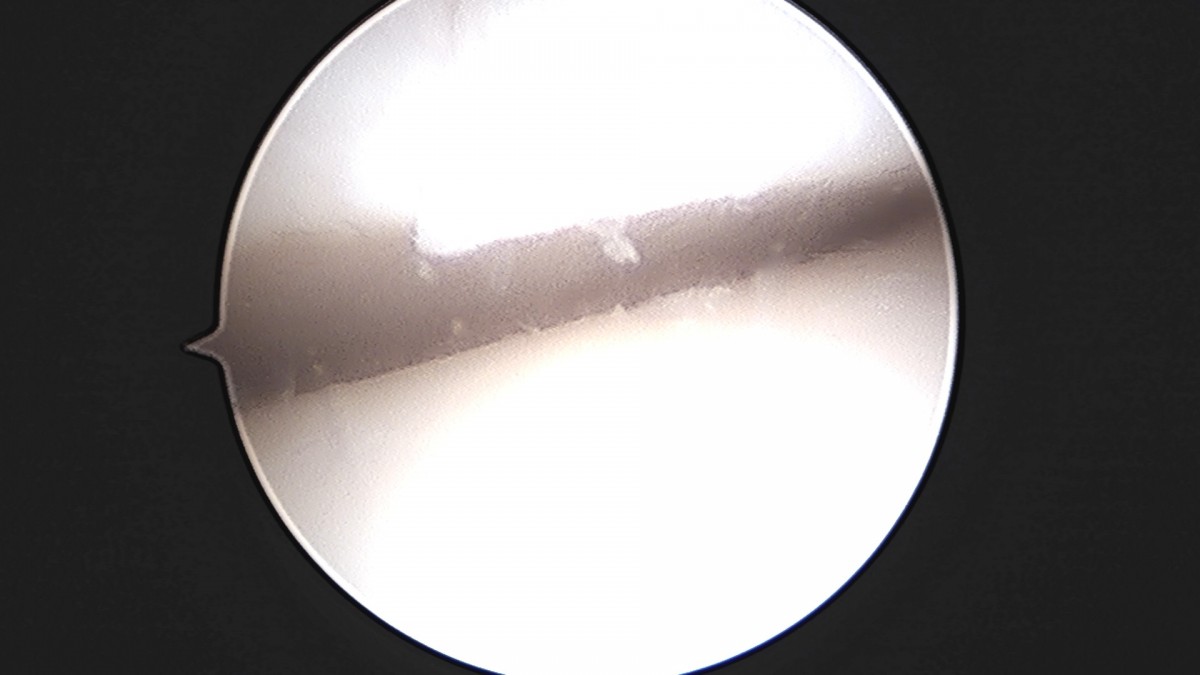

이재상원장님 발목 인대 봉합술 이지O 환자

작성자 최고관리자 댓글 0건 조회 681회 작성일 25-09-16 16:26